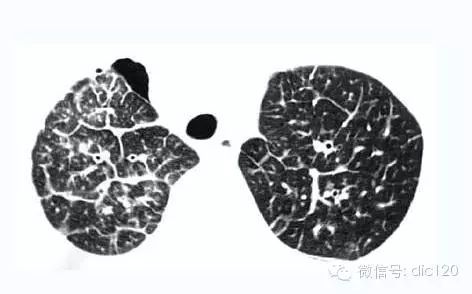

肺結節(pulmonarynodule)通常是指直徑不超過3cm的肺內類圓形病灶,不超過2cm則稱為小結節,其中不超過1cm可稱為微結節。小結節病變的診斷和鑒別診斷一直是放射學的一個難題,如何提高小結節的細節(details)顯示是其中的關鍵。俗語“巧婦難為無米之炊”,對於一個毫無特征可言的肺結節,再高明的醫生也難下結論,而對一個特征詳盡的肺結節,即使一個初驗者也有同樣準確的答案。隨著螺旋CT的出現,小結節的細節顯示和準確診斷率得到明顯的提高。

對於一個周圍性肺結節,特征顯示包括三方麵:形態學特征、結節-肺界麵和鄰近改變;血管改變貫穿以上三方麵。